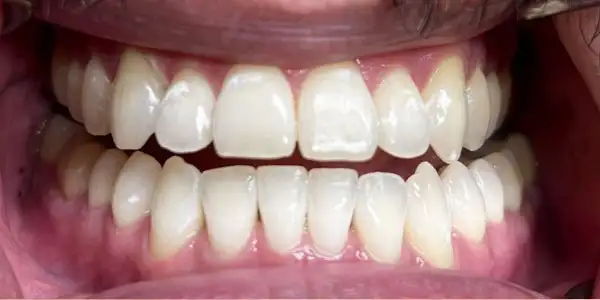

Enhances the appearance of your smile using:

- Smile designing

- Veneers

- Tooth reshaping

- Gap correction

Improves tooth shape, color, alignment, and overall smile harmony. Perfect for confidence and aesthetics.